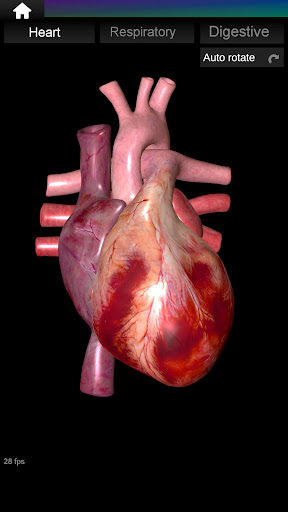

* Heart, which includes the atria, ventricles, aorta and an animation of this organ.

Shows a 3D anatomical model of the main organs of the human body and a description of each one.

* Easy to access and navigate (zoom, 3D rotation).

* Hide or show information.

* Descriptions of each organ.